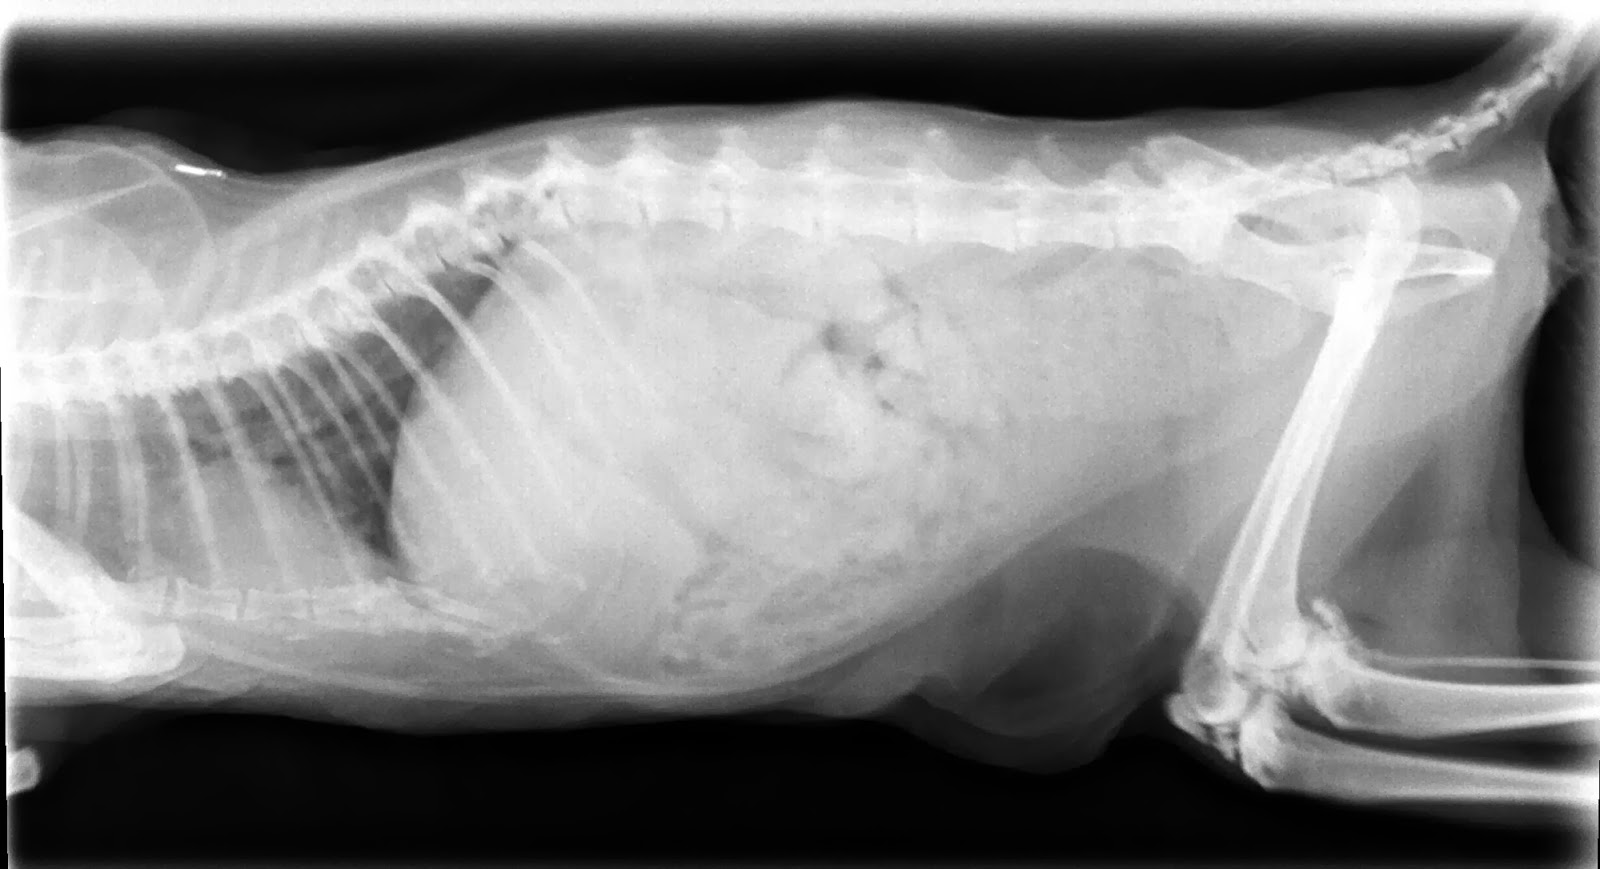

Xrays Of Fluid Or Mass In A Cat S Chest Ask A Vet